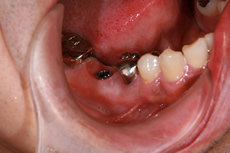

術中

新しい歯の土台作り

局部麻酔を行ったあと、顎の骨にインプラントを埋め込みます。このインプラントが新しい歯の土台となります。手術後は、インプラントと骨が結合するまで待ちます。様々な条件によって期間が異なりますが、2ヶ月~半年が目安となります。